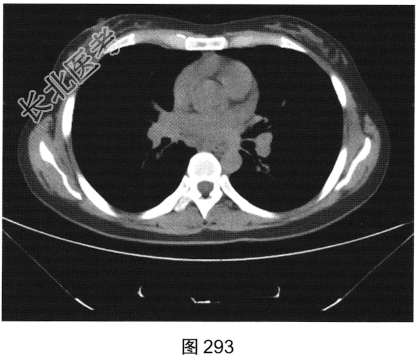

- [材料题] 患者女性,43岁,因“确诊肺低分化腺癌1周”就诊。患者于2014年11月无明显诱因出现咳嗽、咳痰,无胸闷胸痛,无咯血,无发热、乏力、体重减轻等。自服中药治疗,止咳效果尚可。2015年4月22日在山海关人民医院行胸部CT:显示①慢性支气管炎继发感染,建议结合临床及病史考虑;②右侧中间段支气管及中叶支气管壁增厚、管腔狭窄伴右肺中叶阻塞性肺不张,右侧肺门及纵隔多发淋巴结增大,建议增强扫描。后补做增强CT:右肺中叶支气管增厚,管腔狭窄伴阻塞性肺不张,考虑右侧中心型肺癌伴纵隔多发淋巴结增大,建议行支气管镜检查。支气管镜取活检病理:示低分化腺(右肺中叶)癌,建议做免疫组织化学检测,以进一步明确诊断。于北京肿瘤医院行PET/CT检查:①右肺中叶支气管起始部位高代谢结节,符合中心型肺癌表现;右肺中叶部位阻塞性不张,不张肺内高代谢结节,倾向肺内转移;双肺多发转移结节;双锁骨上区、左胸肌间、纵隔及双肺门多发淋巴结转移。②脑部未见明显高代谢征象,建议行增强MRI检查。③双叶甲状腺炎性或非特异性摄取,建议行B超及甲状腺功能检查。患者精神状态良好,体力、食欲、睡眠均正常,体重无明显变化,大便、排尿正常,为进一步检查及治疗,门诊以“肺癌”收入院。2015年5月5日在我院行CT检查,如图288~图295所示。